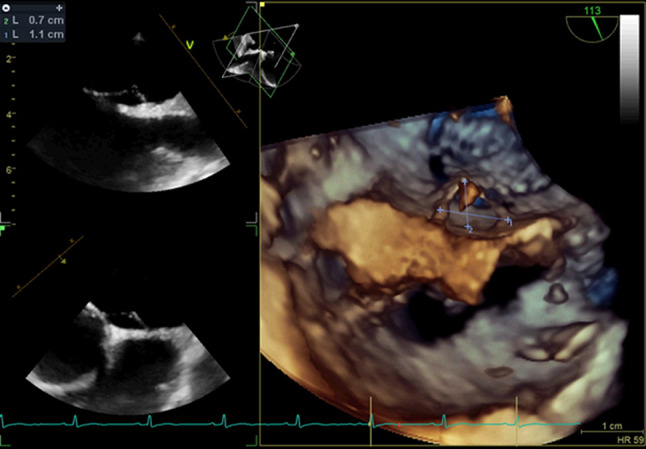

Methods: Data on all patients who underwent PFO closure from 2016 to 2022 were collected. Anatomical characteristics were measured using transesophageal echocardiography and analyzed by two cardiologists.

Abstract Image